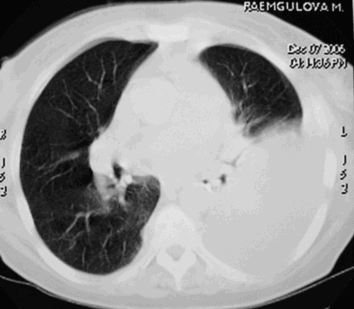

Плеврит